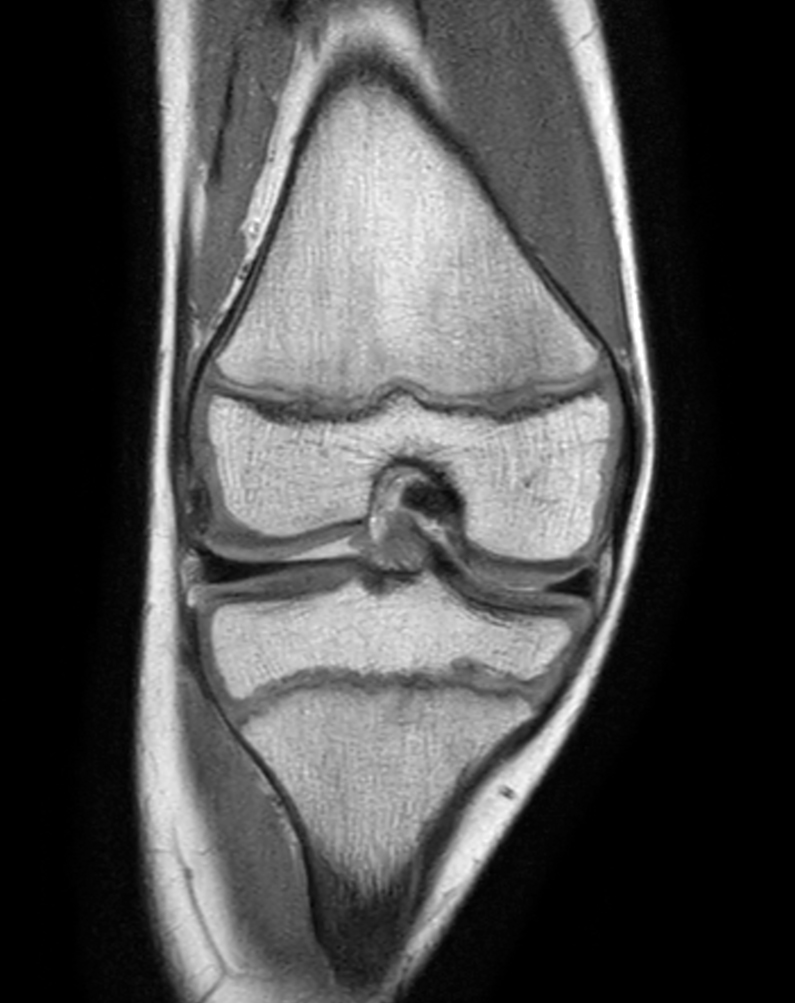

Coronal PDw TSE